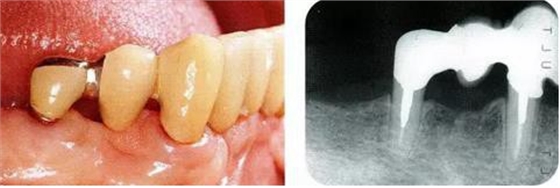

病例4維系鄰牙的骨水平的戰(zhàn)略性拔牙:

圖17-1 ( 左 ),2 ( 右 )▲右下4近中9mm的骨緣下缺損,兩側(cè)全口橋體修復(fù),但是這顆患牙保留的情況下會影響牙列的維持,鄰接牙的骨水平在較高的位置,拔牙后可以獲得平坦的骨水平。即使是右下4嘗試再生療法,假說可以100%的成功,右下3遠(yuǎn)中骨水平也會形成3mm以上的臺階。而且再生治療也需要患者登上1年半以上的時間。所以最終選擇拔牙的處理。